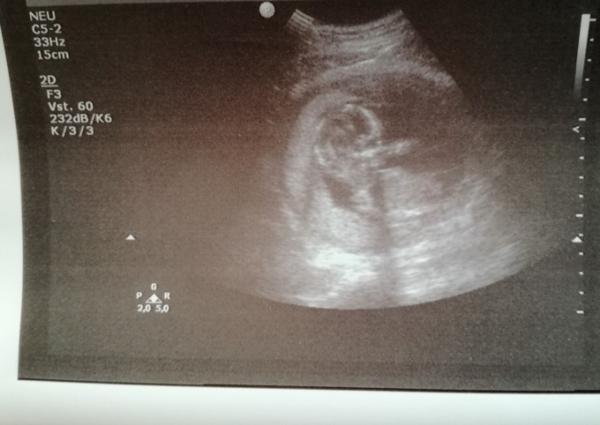

Hier mein US Bild von heute 16. SSW

Ich erkenne da ja mal.gar nichts.

Auf den Ultraschall unten sieht man schön das Köpfchen.